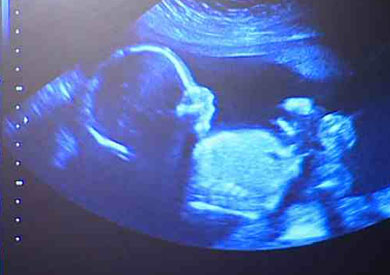

حصل الأطباء في بريطانيا على الموافقة لإجراء أول عمليات لزرع عشرة أرحام عقب نجاح هذه العملية في السويد، وذلك بعد جهود استمرت عشرين عاما.

وفي حال نجاح التجربة، فإن أول طفل يولد في بريطانيا من رحم مزروع سيصل إلى عالمنا في أواخر عام 2017 أو 2018.